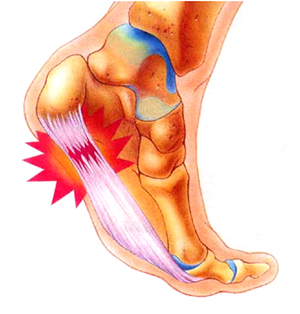

족저근막은 발바닥의 두꺼운 섬유질 막으로 발의 아치를 형성하고 걸을 때 발을 강력하게 지지해줍니다. 걸으면서 발뒤꿈치를 올리면 발뒤꿈치의 족저근막 부착 부위에 높은 장력이 가해집니다.

특히 달리기와 같은 활동 중에는 더 높은 장력이 가해져서 족저근막 부착 손상의 위험이 증가하게 됩니다. 족저근막염은 가벼운 부상이나 과도한 사용으로 인한 염증으로 발뒤꿈치와 발바닥에 통증을 일으키는 질환입니다. 아침에 일어나서 방바닥에 발을 딛는 순간 통증으로 깜짝 놀라는 경험을 해보신 적이 있다면 족저근막염 증상을 의심해봐야 합니다.

족저근막염은 외부 요인에 의해 갑자기 발생하는 것이 아니라 서서히 증상이 진행되는 것을 볼 수 있습니다. 발뒤꿈치 중앙보다 약간 앞으로 뻗어 있으므로 내측에서 발생하고, 아침에 일어나거나 오래 앉아 있다가 갑자기 일어날 때 강도가 높게 나타납니다. 잠을 자거나 앉는 것처럼 몸이 이완된 상태에서 움직이면 갑자기 늘어나 통증이 오게 됩니다.

통증은 일반적으로 발뒤꿈치 안쪽과 바닥에서 느껴집니다.